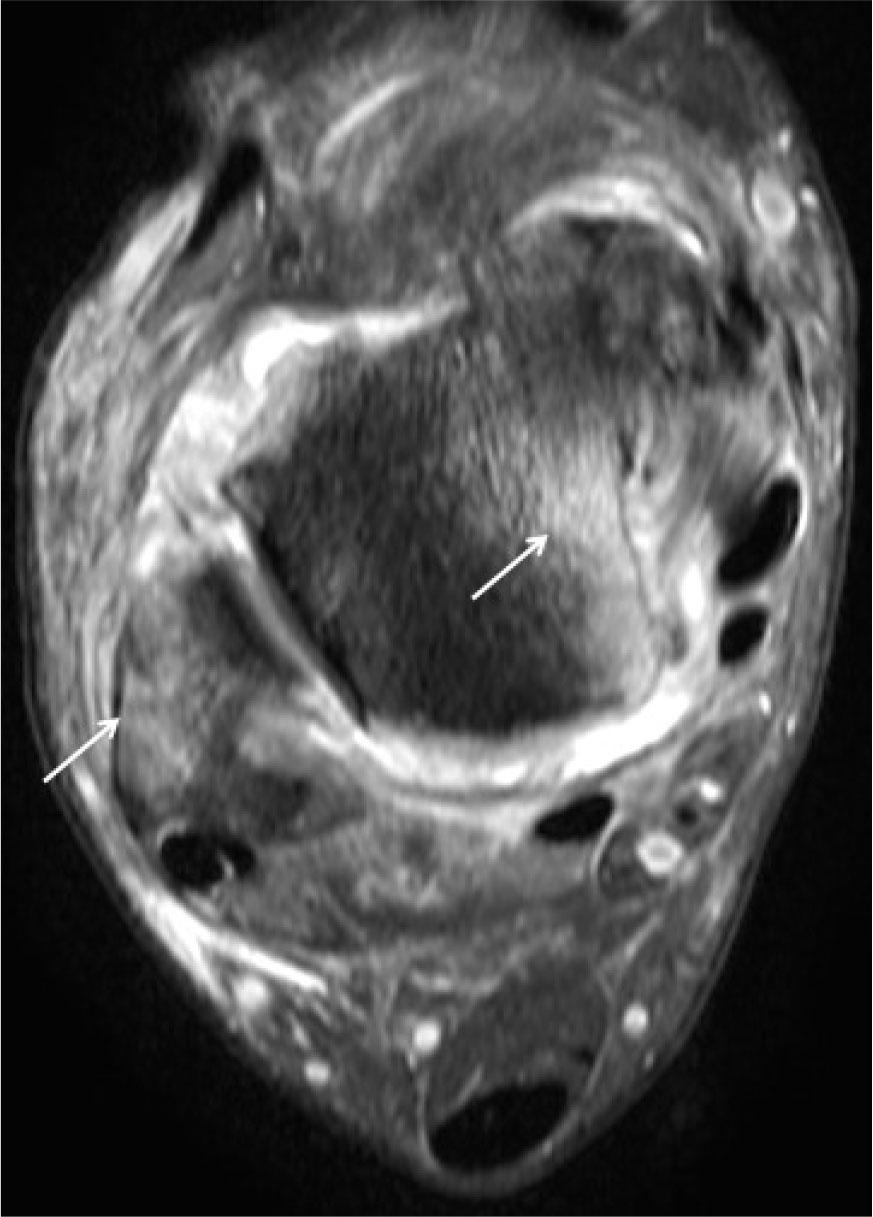

Fig. 19.

Enthesitis. MR proton density fat-suppressed coronal (A and B) and axial images of the ankle show extensive marrow edema (hyperintensity) at the attachment sites of ligaments (small arrows in A and C); retinaculum (arrows in B) and fascia (long arrow in C)